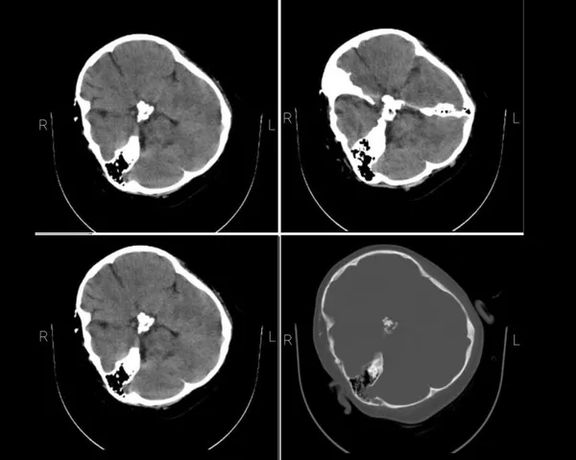

Iran International obtained Amini’s brain CT scan from hospital sources in September that shows serious injuries to her skull. Hospital staff also confirmed that she was in a coma upon arrival. Fars news agency affiliated with the Revolutionary Guard confirmed that the CT scan belonged to Amini. Moreover, her photos in the hospital show her bleeding from the right ear, a definite sign of brain injury.